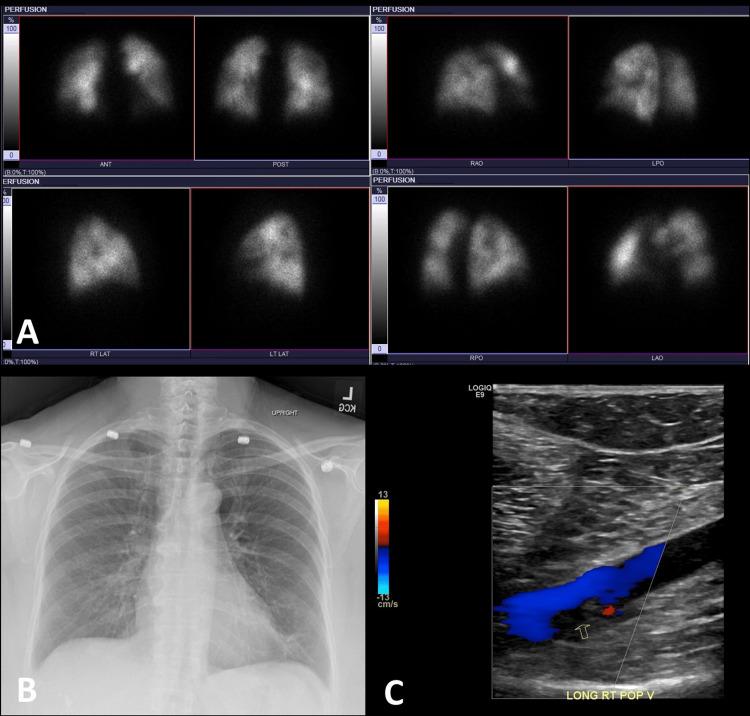

Introduction The COVID-19 pandemic has profoundly impacted medical practices, including nuclear medicine. To minimize aerosol transmission risks, lung perfusion scintigraphy was preferred over traditional ventilation-perfusion (V/Q) scintigraphy during the pandemic. This study compares lung perfusion scans performed during COVID-19 with V/Q scans from the pre-COVID era. After reviewing this study, the reader will learn about V/Q scintigraphy and lung perfusion. Methods This retrospective observational study, conducted from December 2018 to July 2021, involved 868 patients - 511 in the pre-COVID era and 357 in the post-COVID era - at a single tertiary care center. The pretest probability of pulmonary embolism (PE) was determined using Wells' criteria, and data including demographics, clinical findings, and diagnostic test results (V/Q or lung perfusion scintigraphy) were collected. Results A 30% decline in lung scans was observed during the pandemic. In the pre-COVID era, 68.3% of scans had low, 27.8% had intermediate, and 3.9% had high probability for PE. During the pandemic, perfusion-only scans showed 57.3% low, 32.9% indeterminate, and 9.8% high probability for PE. Among COVID-19-positive patients, 48.9% had intermediate, and 11.1% had high probability scans. The rise in indeterminate and high-probability scans during the pandemic is attributed to COVID-19-related lung changes and hypercoagulability. Conclusion The perfusion component of lung scans is typically sufficient for evaluating acute PE. Omitting the ventilation part of the V/Q scan had minimal impact, with only a 5.1% increase in indeterminate/non-diagnostic scans using perfusion-only modified Prospective Investigation of Pulmonary Embolism Diagnosis II (PIOPED II) criteria during the post-COVID-19 era, likely due to underlying lung parenchymal involvement in COVID-19 patients. Additionally, there was a 5.9% rise in high-probability scans, attributed to the hypercoagulability and vascular complications associated with COVID-19.

摘要

引言

新冠疫情对包括核医学在内的医疗实践产生了深远影响。为了将气溶胶传播风险降至最低,在疫情期间,肺灌注闪烁扫描比传统的通气-灌注(V/Q)闪烁扫描更受青睐。本研究比较了新冠疫情期间进行的肺灌注扫描与新冠疫情前时代的V/Q扫描。阅读本研究后,读者将了解V/Q闪烁扫描和肺灌注。

方法

这项回顾性观察研究于2018年12月至2021年7月在一家三级医疗中心进行,涉及868例患者,其中新冠疫情前时代511例,新冠疫情后时代357例。使用Wells标准确定肺栓塞(PE)的预测试概率,并收集包括人口统计学、临床发现和诊断测试结果(V/Q或肺灌注闪烁扫描)的数据。

结果

疫情期间观察到肺扫描下降了30%。在新冠疫情前时代,68.3%的扫描PE概率低,27.8%为中等,3.9%为高概率。在疫情期间,仅灌注扫描显示57.3%概率低,32.9%不确定,9.8%概率高。在新冠阳性患者中,48.9%为中等概率,11.1%为高概率扫描。疫情期间不确定和高概率扫描的增加归因于与新冠相关的肺部变化和高凝状态。

结论

肺扫描的灌注部分通常足以评估急性PE。省略V/Q扫描的通气部分影响最小,在新冠疫情后时代,仅使用灌注的改良肺栓塞诊断前瞻性调查II(PIOPED II)标准,不确定/非诊断性扫描仅增加了5.1%,这可能是由于新冠患者潜在的肺实质受累。此外,高概率扫描增加了5.9%,这归因于与新冠相关的高凝状态和血管并发症。